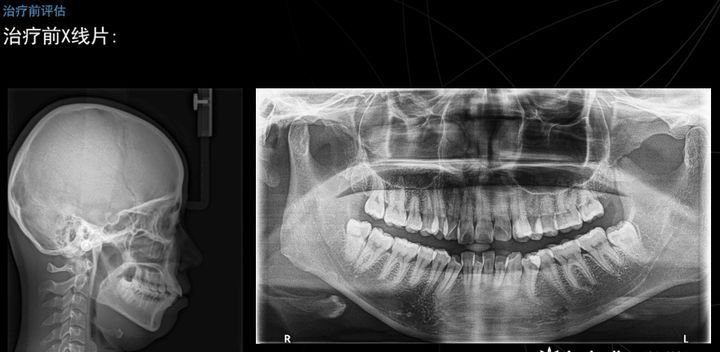

姑娘主诉:嘴突,牙齿非常不整齐,笑起来虎牙不美观,有开唇露齿现象.

想做口腔矫正,年龄23岁,照x光片以后发现,门牙后面有一颗埋伏牙(虎牙)

想做口腔矫正年龄23岁照x光片以后发现门牙后面有一颗埋伏牙虎牙是拔